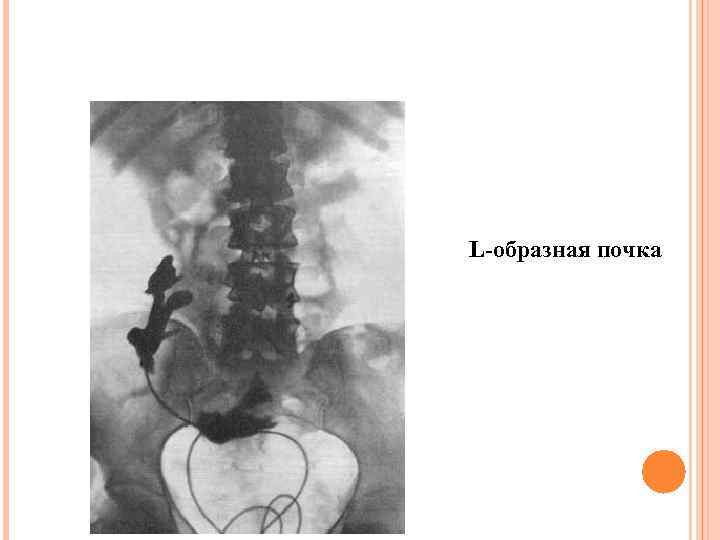

Асимметричные формы сращения S-образная почка L-образная почка I-образная почка

Асимметричные формы сращения S-образная почка L-образная почка I-образная почка

L-образная почка

L-образная почка